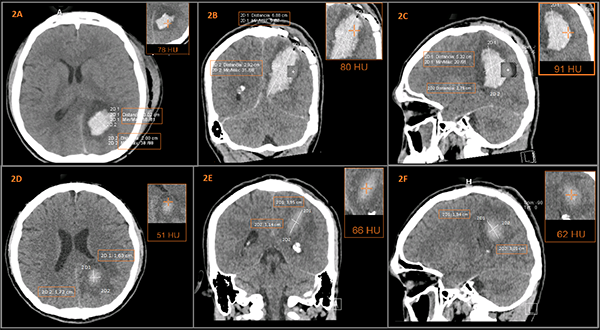

Paciente masculino de 24 años de edad, referido desde un hospital de primer nivel, tras sufrir agresión física con arma blanca a nivel de región parietal izquierda de aproximadamente 3 cm, ingresa por presentar cefalea holocraneana de gran intensidad, desorientación y disminución de la agudeza visual. Por antecedente de trauma y al contar únicamente con radiografías se realizan 2 placas: Antero-Posterior y Lateral de Cráneo (Rx AP y Lat) observándose cuerpo extraño con densidad metal compatible con la “Hoja de un Cuchillo” (Figura 1A).

Es transferido a un hospital de tercer nivel, donde es valorado por el servicio de Neurocirugía, evidenciando al ingreso en el examen neurológico: desorientación, parafasias, dislalia, disartria, acalculia, disociación derecha izquierda, hemiparesia facio braquio crural con fuerza muscular (FM) 4/5, isocoria, normoreactividad y disminución de la agudeza visual. Con una puntuación de Glasgow de 14/15, hemodinámicamente estable y afebril. TC Simple de Cráneo evidencia a nivel de la región parietal izquierda una imagen con densidad metálica. La reconstrucción 3D confirma la presencia de la “hoja de un cuchillo” intraparenquimatoso, sin compromiso vascular en la AngioTC (Figuras 1B y 1C).

Figuras 1: A)

Radiografía AP y Lat: Evidencia de Imagen de Cuerpo Extraño con densidad Metal “Hoja de un Cuchillo”. B) TC Simple de Cráneo con Reconstrucción 3D: Evidencia de cuerpo extraño en región parietal izquierda. C) AngioTC: Ausencia de lesión vascular, se visualiza Polígono de Willis sin alteraciones. D) Medición de Cuerpo Extraño. E) Visualización tras apertura de duramadre de “hoja de un cuchillo incrustado” a nivel de parénquima cerebral. F) Extracción completa de la “hoja de un cuchillo”.